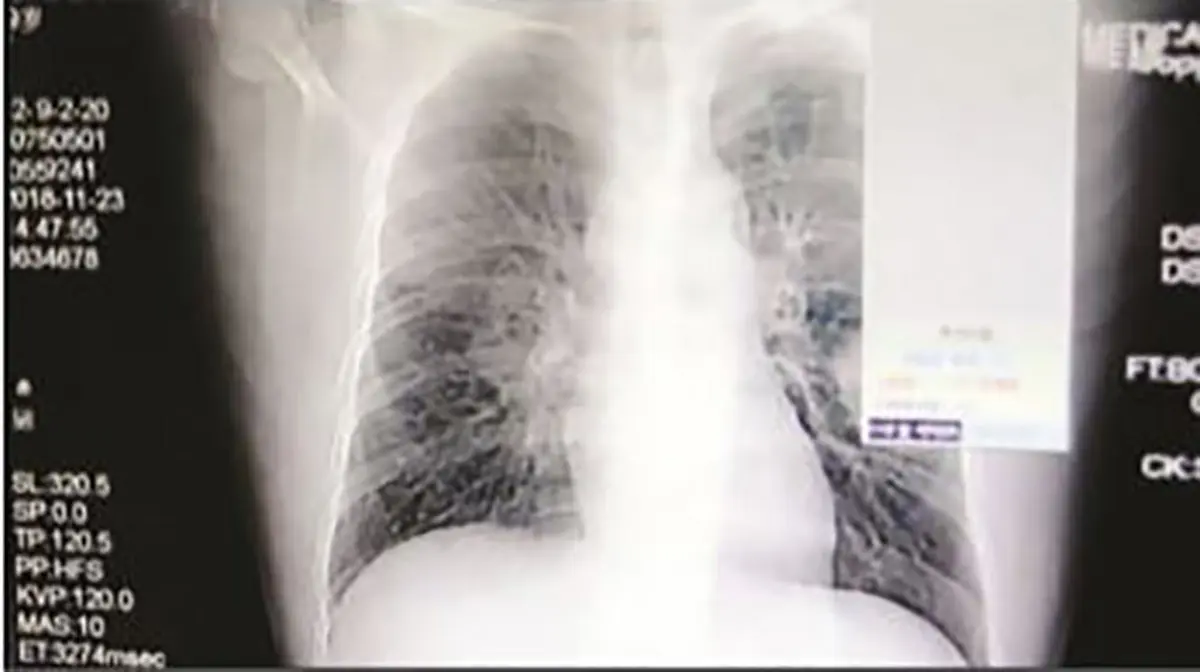

حوادث رکنا: مردی در چین که عادت داشت جورابهایش را هر شب بو کند، دچار عفونت ریه شد و سرانجام جان باخت.

به گفته پزشکان و به گزارش میرور، افراد وسواسی که عادت دارند جوراب یا حتی کفشهای خود یا فرزندانشان را بو کنند، میتوانند قربانی این عفونتهای ریه باشند. به گفته متخصصان، انواع قارچها و دیگر عوامل بیماریزا در جورابها وجود دارند و ذره کوچکی از آنها میتواند موجب بیماری فردی شود که آنها را استنشاق میکند.اخبار 24 ساعت گذشته رکنا را از دست ندهید